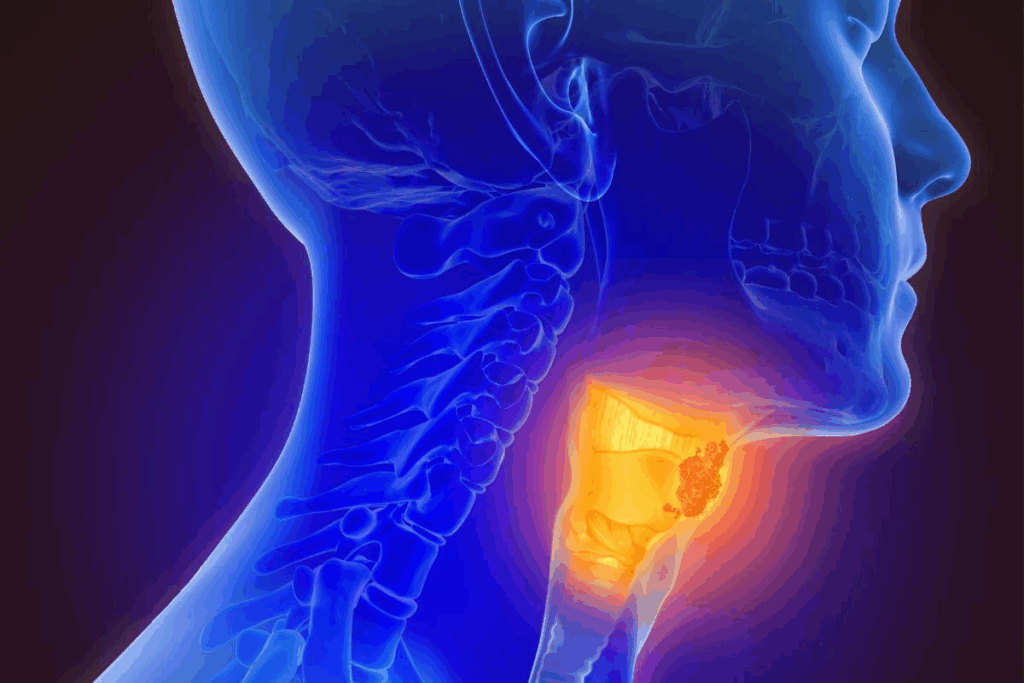

Overview of Oral Cancer

Oral cancer is a group of cancers found in the mouth and nearby areas. It’s a big health issue worldwide. There are different types and risk factors for it.

Common Sites of Occurrence

Oral cancer can pop up in many parts of the mouth and oral cavity. The most common spots are:

- The tongue

- The floor of the mouth

- The lips

- The gums and other areas of the oral cavity